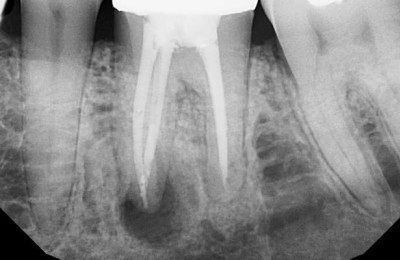

Апикальный периодонтит

В некоторых случаях толщина костной стенки между слизистой оболочкой и корнем составляет менее 1 мм. В таком случае любой воспалительный процесс в верхушке корня может послужить причиной гайморита.

Одним из самых распространенных, «безобидных» на первый взгляд, но очень серьезных заболеваний зубов является кариес – поражение происходит по самый корень и после влечет за собой воспаление. Периодонтиты, кисты и пародонтиты способствуют истончению костной стенки альвеолярного отростка верхней челюсти.

Воспаляется прилежащая слизистая оболочка, после начинает скапливаться экссудат и нарастает давление в полости пазухи, возникают жалобы и клиника гайморита.

Данная анатомическая особенность выявляется с помощью рентгенологического исследования. Если она присутствует, нужно уделять особое внимание гигиене полости рта для профилактики заболевания.